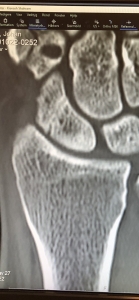

Läkarbesök med handen, nu måste detta få ett slut!

Måste först säga att det här med sjukhusbesök och prata med läkare börjar bli min vardag. (Känns snart som jag kan börja sätta diagnoserna innan läkaren träffats haha)Jag var som sagt på ortopedmottagningen på SÄS igår för att kolla upp min hand igen, det är ju 10 månader sedan jag kraschade och jag har kärt […]